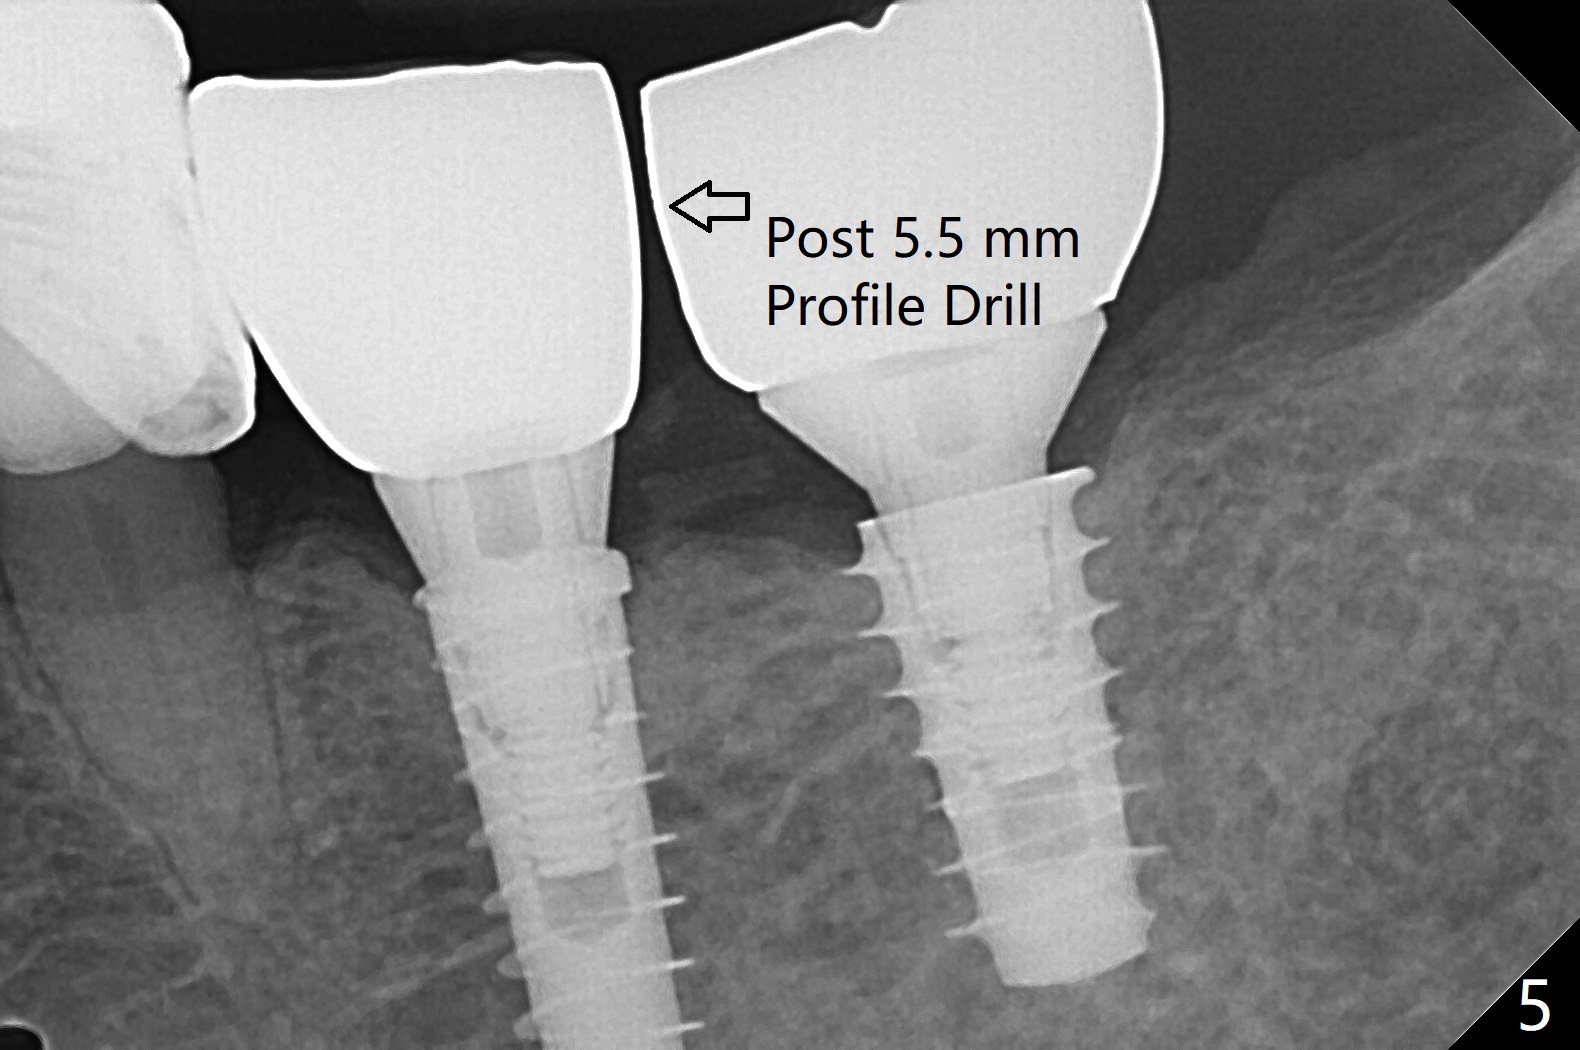

Because of the narrow ridge top at the sites of #19 and 18, it is reduced (Fig.1 arrowheads) prior to initial osteotomy with 1.6 mm pilot drill. After Magic Drills (3.3 and 4.3 mm at #19 and 18, respectively), 4x11 and 5x9 mm IBS implants are placed with insertion torque >35 Ncm with immediate placement of pair abutments (4.5x5.7(2) and 6.5x4(2) mm, Fig.2). In fact these sites are converted to a premolar and a 1st molar (because narrow ridge at #19). Following GBR and suturing, periodontal dressing is applied around the abutments for increased retention. The regional ridge reduction makes Marking Bur unnecessary (because of flat ridge top and the soft bone in this case) and more importantly there is no thread exposure upon implant placement. The trimmed site (concavity) is favorable for bone graft and membrane placement. One month postop, loose perio dressing is removed and replaced by a splinted nonfunctional provisional. The implant sites look normal nearly 3 months postop; there is no bone loss (Fig.3). Impression is taken. The crown/abutment at #18 is loose 3 years 2 months post cementation; when the crown/abutment is retightened, the abutment remains incompletely seated (Fig.4 <) in spite of reduction of the proximal contact (arrow). It may be due to the block of the distal crest (*). After use of 5.5 mm profile drill, the 6.5x4(2) mm abutment remains unseated (Fig.5). The smaller one (5x4(2) mm, Fig.6) is seated. When the redo crown is cemented, the surrounding gingiva is healthy with a short papilla between the implant crowns (Fig.7).